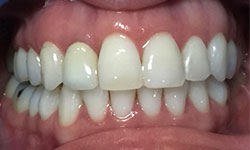

(29)

Before Treatment

After Treatment

Patient reported to our clinic with a dental concern in upper teeth. We had performed root canal treatments in upper teeth followed by fixed partial denture. Post the treatment due to bone loss upper teeth were extracted followed by Dental Implants. 6 Dental implants were placed in the upper jaw. 3 months period was followed allowing integration of implants to the bone ,post which prosthesis were delivered to the patient.